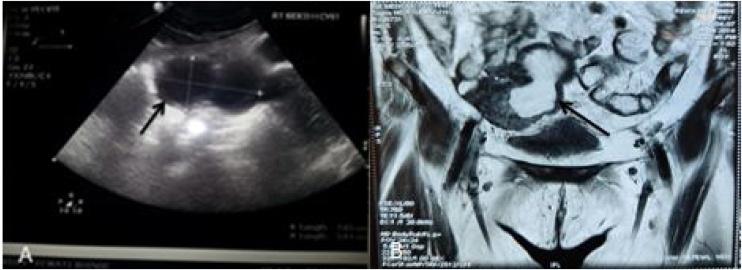

We hereby report the case of a 44-year-old woman who had concurrent large isolated cecal endometrioma, which was diagnosed pre-operatively on imaging to be pelvic endometriosis/hematosalpinx and solitary retroperitoneal cellular leiomyoma, which was incidentally identified. Both the conditions were managed successfully by laparoscopy.

我们在此报告一例44岁女性,她同时患有巨大孤立性盲肠子宫内膜瘤,术前影像学诊断为盆腔子宫内膜异位症/输卵管积血,以及偶然发现的孤立性腹膜后细胞性平滑肌瘤。这两种病症均通过腹腔镜手术成功治疗。